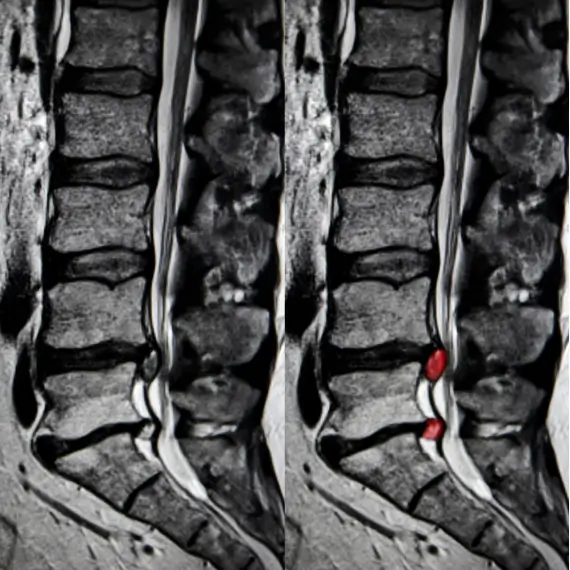

Common causes of sciatica include:

- Herniated disc

- Bulging disc

- Spinal stenosis

- Spondylolisthesis

- Degenerative arthritis

- Muscle spasm

- Muscle inflammation

- Malignancy

- Epidural hematoma

- Epidural abscess

Review diagnostics. Do you already have diagnostic tests with you to review with Dr. Fierro? If not, he will order some to confirm a sciatica diagnosis and rule out other underlying conditions.